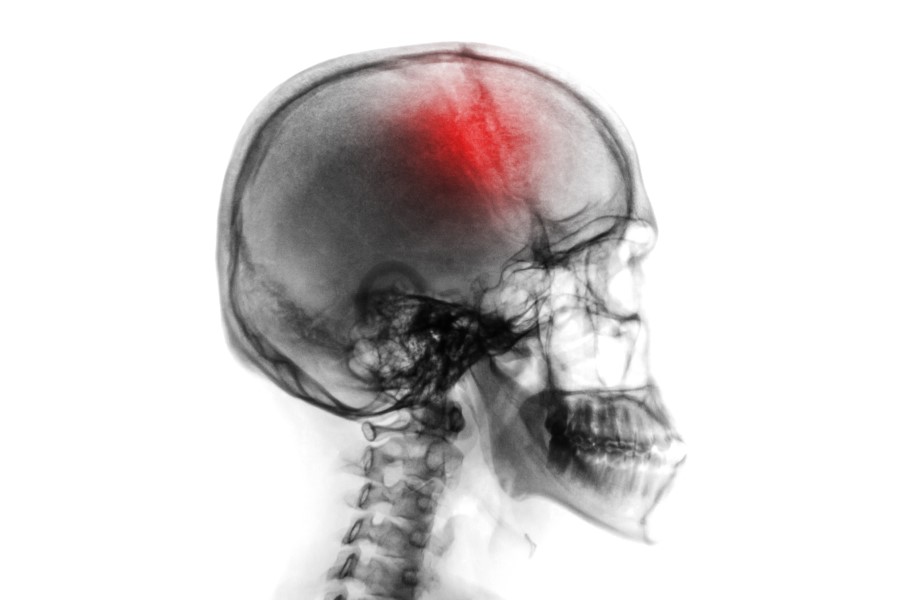

Choroby naczyniowe mózgu stanowią ogromny problem wśród społeczeństwa, gdyż mogą dotknąć wszystkich — w każdym wieku, a ich pierwsze objawy mogą być trudne do rozpoznania. Wśród najczęstszych chorób naczyniowych wymienia się między innymi udar mózgu. Jakie są objawy udaru mózgu, jak rozpoznać objawy ostrzegawcze udaru oraz w jaki sposób zareagować, by pomóc osobie, która doświadcza udaru?

Definicja Światowej organizacji Zdrowia opisuje udar mózgu jako nagły stan zagrażający życiu, którego objawy utrzymują się dłużej niż 24 godziny, wiążą się z uogólnionymi lub ogniskowymi zaburzeniami pracy mózgu oraz wymagają pilnej hospitalizacji. Dwa główne typy udarów to udar niedokrwienny (zawał mózgu) i udar krwotoczny (wylew). W tym artykule zostanie też poruszony temat TIA, czyli przemijającego udaru. Czym one się różnią? Jak je rozpoznać?